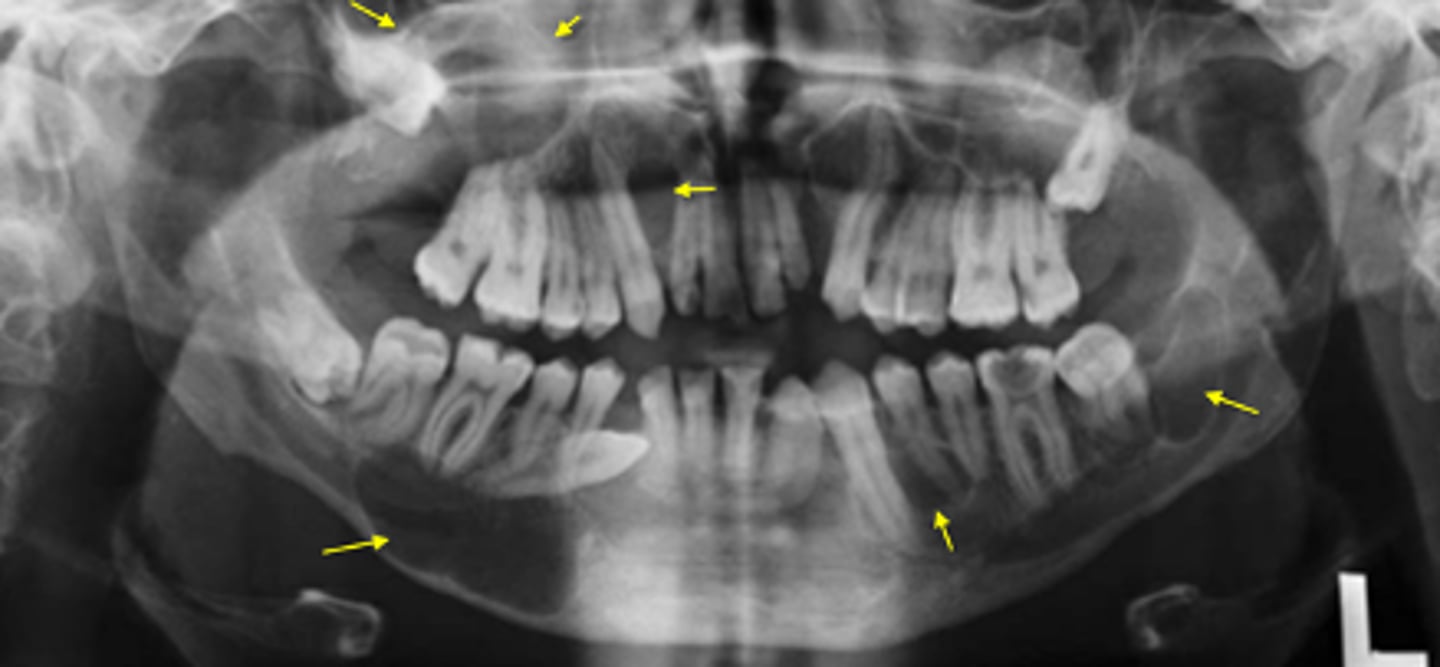

How would you describe the lesion?

- Generalized reduced trabecular bone density in maxilla and mandible

- The teeth appear to be more prominent with the lacking osseous support. Lamina dura not very distinct in multiple locations.

- There are two large defined radiolucencies located in the posterior mandible

- The right side radiolucency is causing thinning of the inferior mandibular cortex and displacement of inferior alveolar canal

- There is wispy septae noted within

- The left mandibular lesion appears to be defined but scooped out along the alveolar crest

What category would this lesion be part of?

Systemic

What would be a differential diagnosis for this lesion?

Hyperparathyroidism (brown tumor)